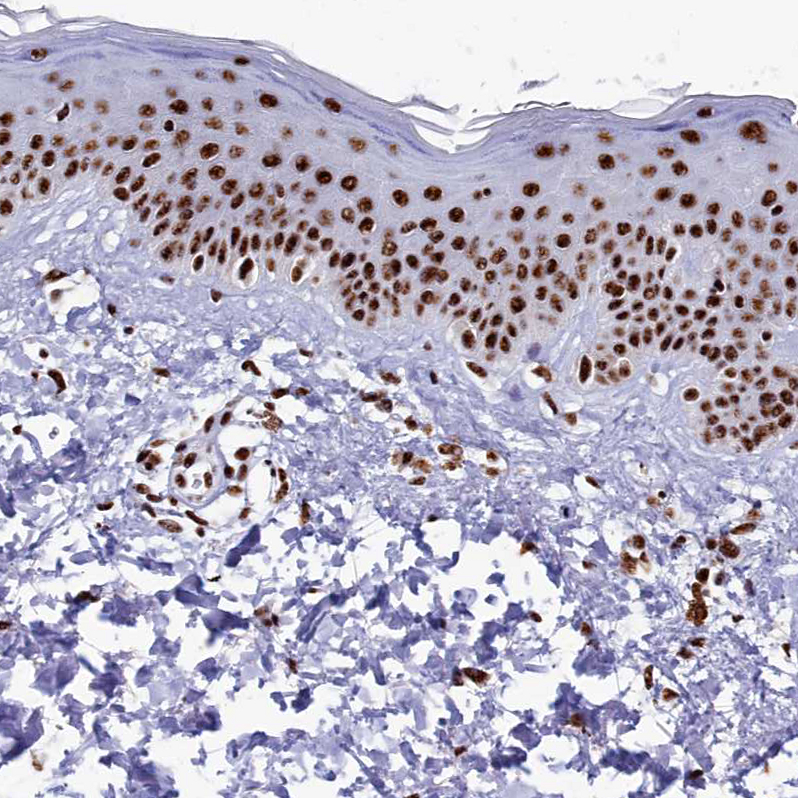

Immunohistochemical staining of human endometrium shows strong nuclear positivity in glandular cells.